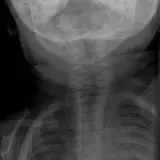

PACSで期待されるツールを完備した完全インタラクティブな症例 — スクロール、ウィンドウ調整、ズーム、パン、計測、ROI、フルスクリーンモード。

重要な所見を症例画像上に直接ハイライトする豊富なアノテーション。症例解説内のリンクされた所見をクリックすると、スキャン上の正確な位置へジャンプできます。

アノテーション付きの画像所見とイラストで効率的に学習